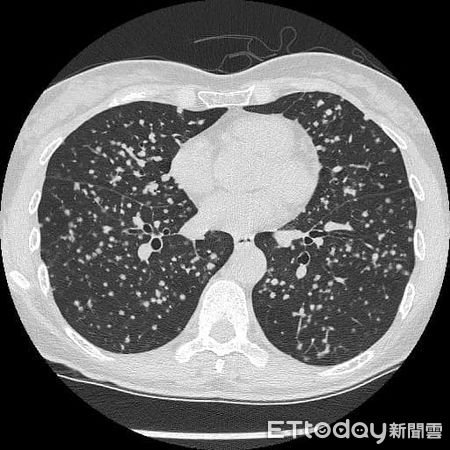

根據《ETtoday》報導,北市聯醫陽明院區胸腔內科主治醫師蘇一峰分享一個案,有一名50多歲的職場女性就醫看診,表示自己近期一直有輕微咳嗽的症狀,原以為是輕微的肺部問題,怎料竟是肺癌末期,甚至已經轉移到體內各處,從X光及電腦斷層檢查來看,肺部整片都是滿天星,白花花一片,醫生也束手無策,生命已開始倒數計時了!

仔細詢問下才知道,這名患者3年多前參加員工體檢時,就曾X光照出1公分的肺部結節,但她忙著工作並不理會它,繼續工作打拚到現在,怎知才3年時間病況就惡化如此快,從X光片能看出左上方肺部已有4、5公分的腫瘤,崩潰表示:「真的只有一點點咳嗽而已......」